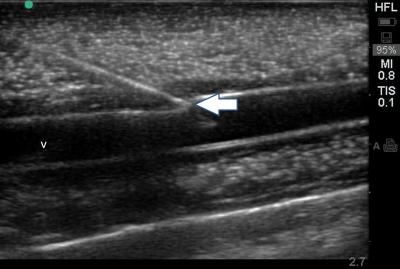

Figure 1: Ultrasonographic image of phantom vessel cannulation using the in-plane approach, with the simulated vein (v) in longitudinal view, and the needle tip (arrow) indenting the vessel wall.